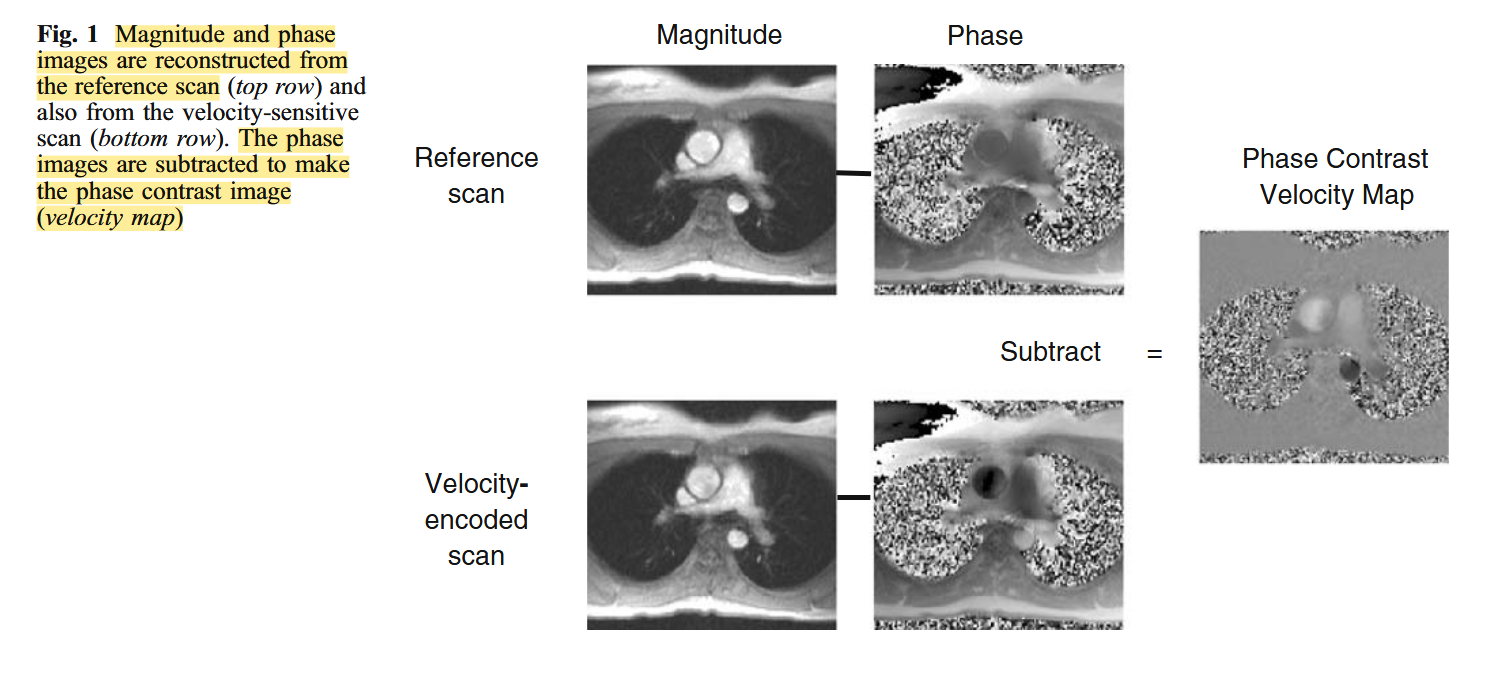

Stationary material is mid-grey (zero-value pixels), with increasing velocities in opposite directions shown brighter (positive pixels) and darker (negative pixels), with an accurate linear relationship to velocity, i.e., . The velocity encoding value should be available as an adjustable sequence parameter. A small represents a highly velocity-sensitive image (Gatehouse et al., 2005).